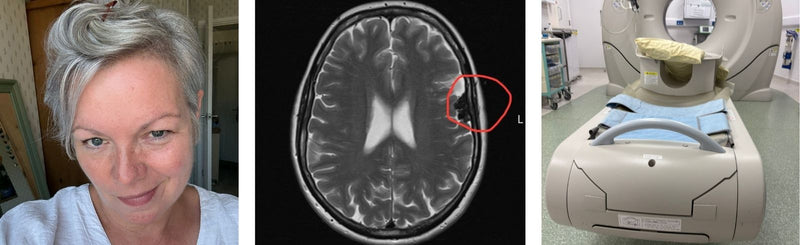

Rhiannon Ashbourne

4 min read